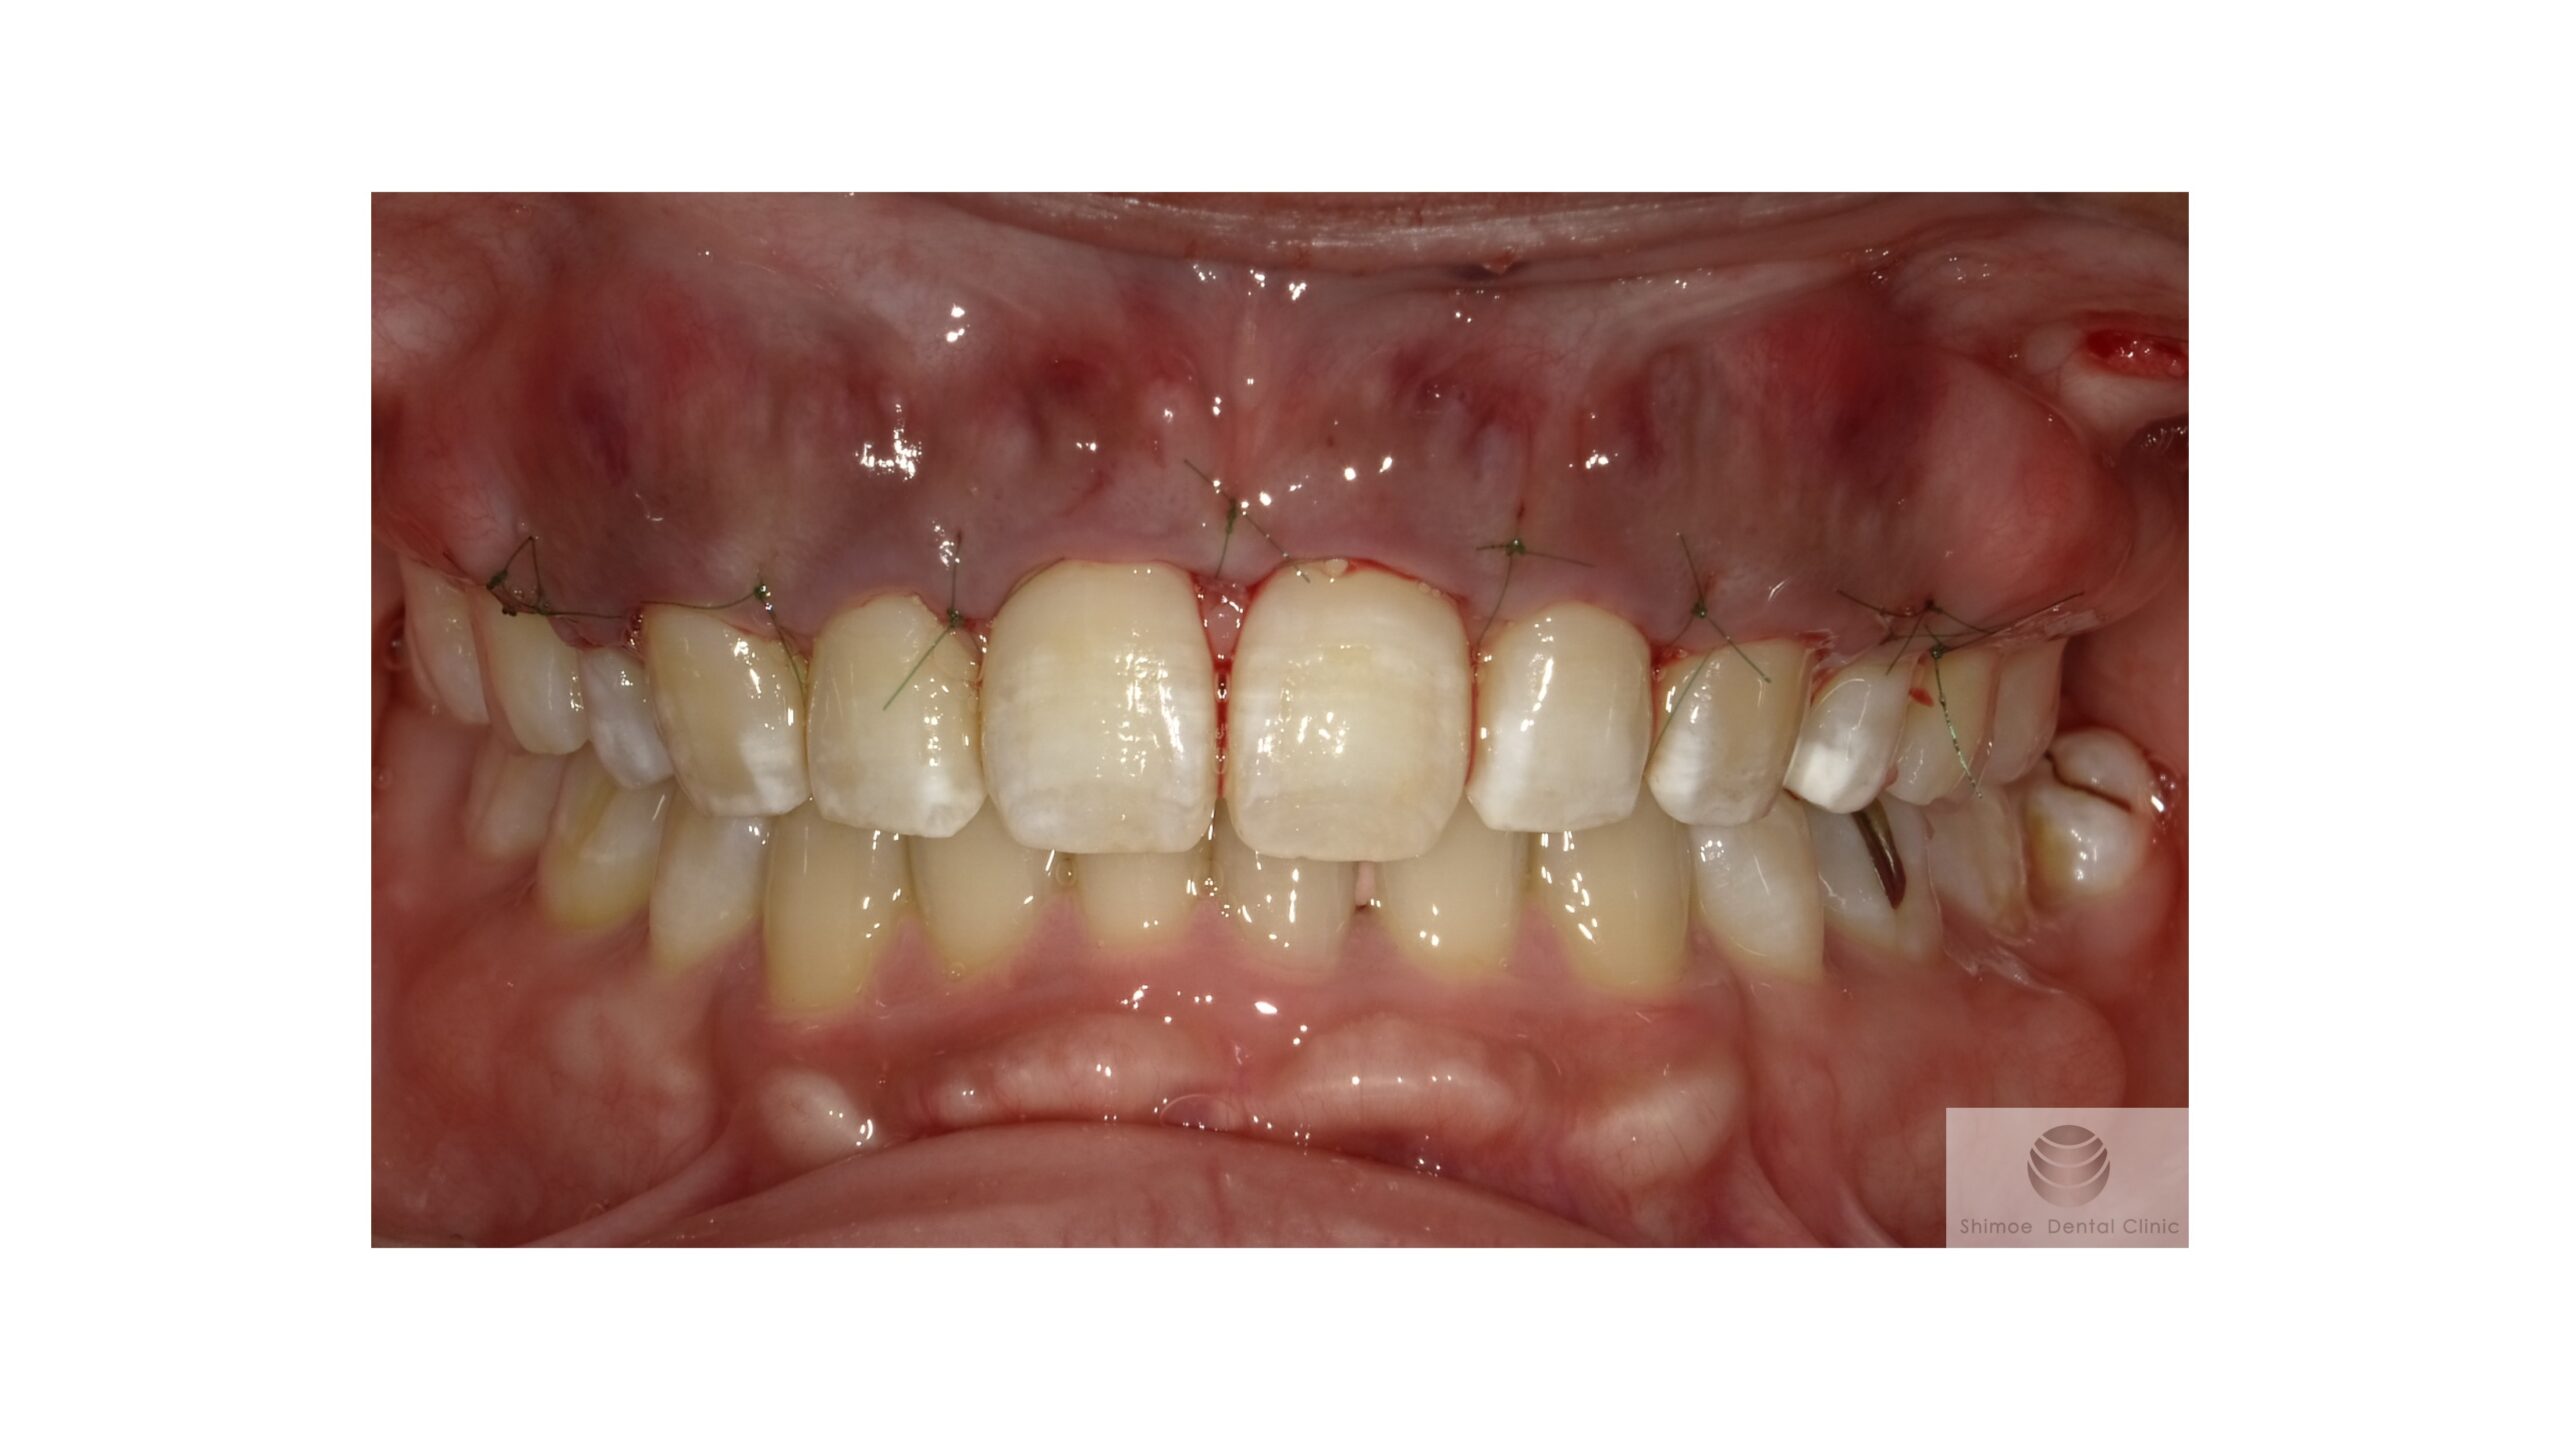

術直後

縫合し手術が終了した状態です。これで、一週間程治癒を待ち、抜糸を行い、数か月経過観察をします。